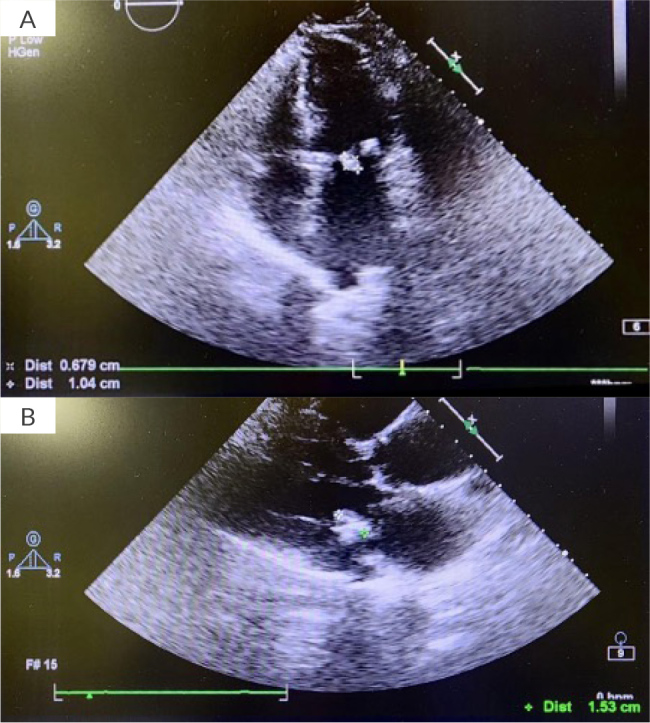

Case presentation: We present the case of a 74-year-old woman from rural Georgia who developed progressive exertional dyspnoea and fatigue. Physical examination revealed multiple murmurs, and transthoracic echocardiography identified a mobile, hyperechoic mass attached to the posterior mitral valve leaflet. Transoesophageal echocardiography raised suspicion for a myxoma or vegetation, and surgical excision was pursued due to embolic risk. Intraoperatively, a teardrop-shaped cystic mass containing multiple daughter cysts was found on the P2 segment of the mitral valve. Histopathology confirmed a hydatid cyst, consistent with cardiac echinococcosis. The patient underwent successful segmental excision of the cyst with mitral valve repair and tricuspid annuloplasty. Her postoperative course was complicated by atrial fibrillation and new-onset type 2 diabetes mellitus. She was treated with albendazole and discharged in stable condition.